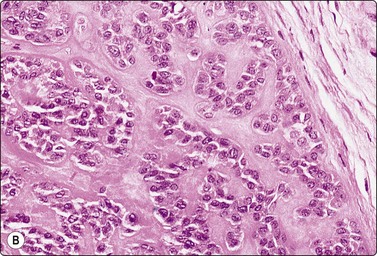

Fig. 4.7 Basaloid squamous cell carcinoma of head and neck

(A) Poorly differentiated cells with squamous features (MGG, HP; (B) Tissue section mimicking adenoid cystic carcinoma (H&E, IP).

Basaloid squamous carcinoma (Fig. 4.7) is a rare distinct variant of squamous cell carcinoma of the head and neck, which is clinically aggressive and has a predilection for the hypopharynx and the tongue. The smear findings are of squamous cell carcinoma without specific features, but a predominance of basal cells may make the distinction from the solid variant of adenoid cystic carcinoma difficult.43